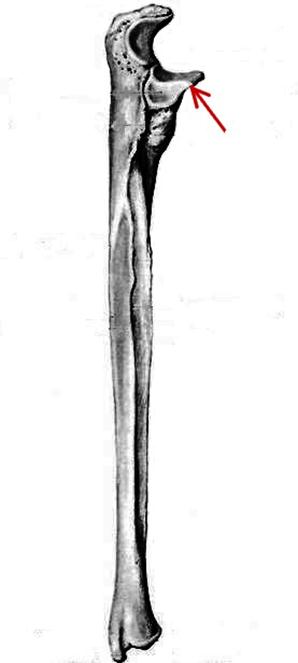

S: На рисунке - ### (латинский язык).

S: Стрелка указывает на... локтевой кости.

S: Стрелка указывает на ### ulnae (латинский язык).

S: Стрелка указывает на ### ulnae (латинский язык).

S: Стрелка указывает на …локтевой кости.

S: Стрелка указывает на … локтевой кости.